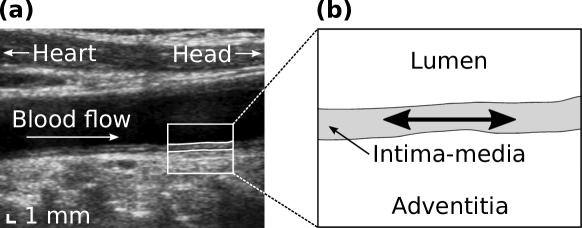

Cardiovascular risk evaluation is a major public health issue as well as a tremendous scientific challenge. In the last recent years, the characterization of the elastic deformation of the tissue layers of the common carotid artery along the direction parallel to the vessel axis during the cardiac cycle in ultrasound sequences (also called cine-loops) has gathered a growing attention. This patho-physiological phenomenon, hereafter dubbed as LOKI for longitudinal kinetics, corresponds to the shear between the intima-media complex and the tunica adventitia (Figure 1) persson2003new . This motion was shown to be cyclic and reproducible over several months ahlgren2012different .

Tracking the motion of the common carotid artery in vivo in B-mode ultrasound image cine-loops is hindered by several factors of different nature. First, the resolution cell of the scanner is generally coarser in the direction perpendicular to the beam () than in the direction of the beam propagation (). This is reflected by the anisotropic shape of the point spread function, whose width (determined by the probe geometry and the depth of the focal zone) is typically larger than its height (determined by the ultrasound signal wave-length) meunier1995ultrasonic . Second, the profile of the image in the longitudinal direction is rather homogeneous and does not present clear landmarks. As opposed to the radial direction, where image intensity undergoes profound variations along the depth of the image, only a small gray level variation is present along the longitudinal profile, as visible in Figure 1. This phenomenon is known as the aperture problem, and in this case, is caused by the geometry of the anatomical structure of the vessel, consisting of tissue layers aligned along the longitudinal axis. As a result, motion along the direction is more difficult to perceive. Third, images are often corrupted by several degrading phenomena inherent to the ultrasound modality itself, such as out-of-plane movements, speckle decorrelation, acoustic shadowing, or movement artifacts, which can lead to the alteration of the tracked speckle pattern over time. Another aspect to consider, especially in the context of clinical routine, is the high variability of image quality caused by the specific vessel geometry and tissue echogenicity of each examined subject.